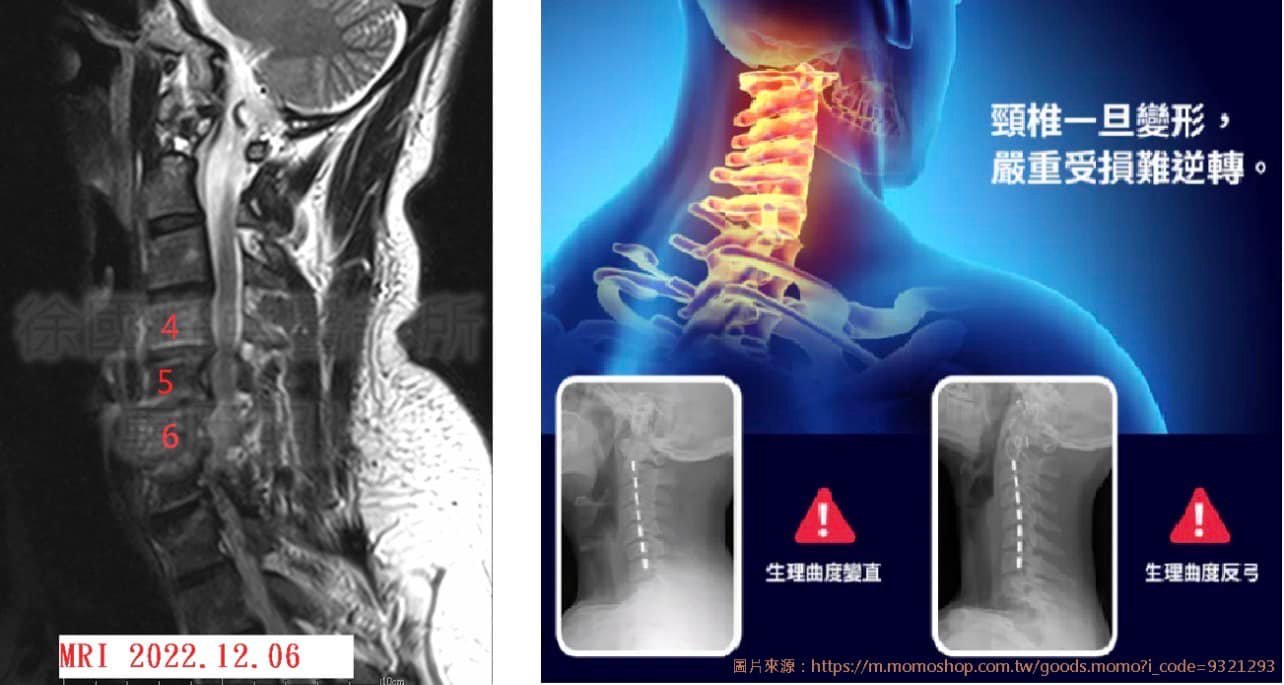

1.頸椎變形

2.C4C5C6輕微脊髓型頸椎病

3.L3L4;L4L5第二級椎孔狹窄

MRI上由於後縱韌帶變厚,脊髓受到了由前向後的壓迫,導致脊髓的壓縮變形,在這個漸進的慢性病程中,如果壓迫損傷加重則可能出現脊髓壞死加重或脊髓軟化病變。